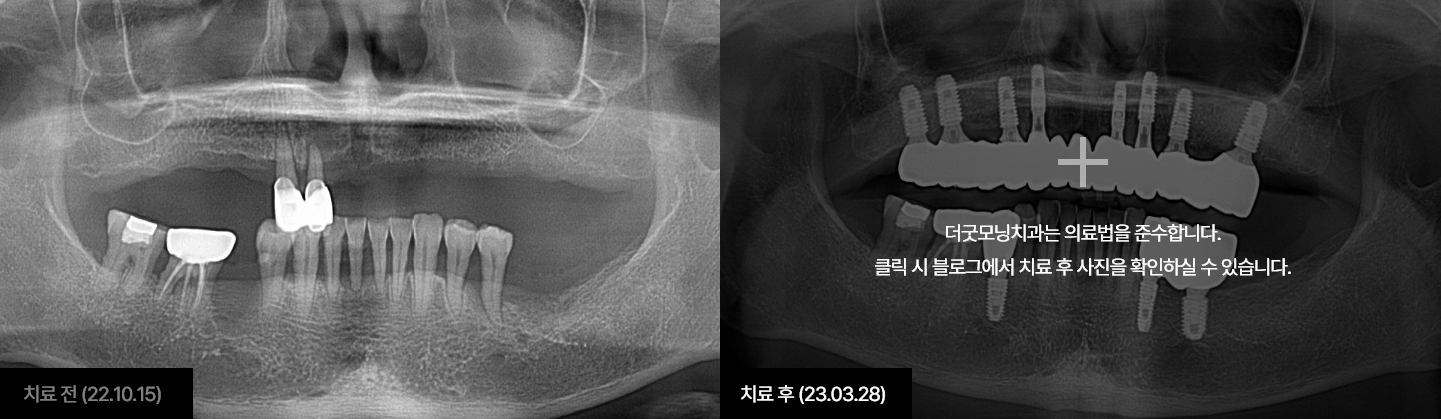

더굿모닝치과 블로그에서 해당 사례를 자세히 확인하실 수 있습니다.

더굿모닝치과는 실제 수술 전, 3차원 3D-CT를 이용하여

정밀진단과 가상수술을 통해 임플란트를 식립할 위치, 방향, 깊이 등

환자 개인의 수술 조건을 사전에 파악하여

한 치의 오차 없이 정확하고 빠르게 완성합니다.